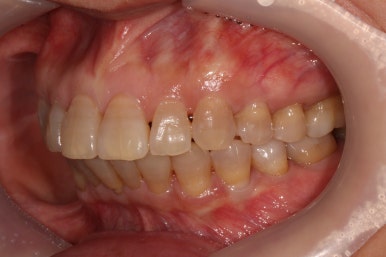

상당히 뻐드러져 있었던 앞니가 적절한 위치를 찾아가고 있는지 확인을 하기 위해 측면 사진도 찍어봅니다.

저희 치과에서는 Overjet이라고 표현하는데, 윗니가 아랫니를 약 1-2mm 정도 덮는 모양이어야 평균이라고 봅니다.

보시면 위와 아래 치아 사이에 약간의 틈이 있는 것을 보실 수 있죠? 점점 개선될거에요!!